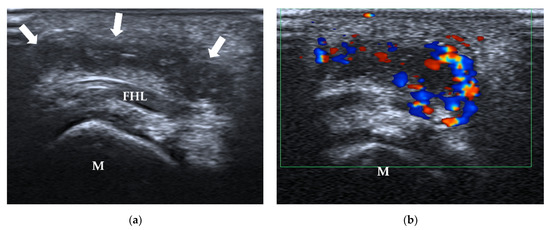

4.2.3. Intermetatarsal Bursitis

| Intermetatarsal bursitis | intermetatarsal spaces between 2nd and 3rd toes | hypoechoic mass with increased vascularity, compressible |